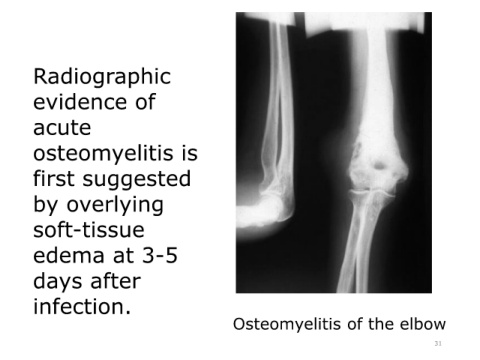

Radiographic

evidence of

acute

osteomyelitis is

first suggested

by overlying

soft-tissue

edema at 3-5

days after

infection.

Osteomyelitis of the elbow